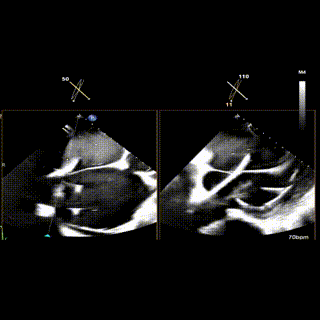

2区

怎么上穿刺鞘攻克巨大左房伴转位穿刺难关!温医大附一院周浩教授团队创新应用“导丝定位+可调弯鞘”技术完成高难度TEER手术_https://www.jmylbn.com_新闻资讯_第5张

3区

怎么上穿刺鞘攻克巨大左房伴转位穿刺难关!温医大附一院周浩教授团队创新应用“导丝定位+可调弯鞘”技术完成高难度TEER手术_https://www.jmylbn.com_新闻资讯_第7张

1.二尖瓣重度关闭不全(4+),瓣环明显扩大(AP径4.6cm,LM径3.9cm),扁平,关闭时瓣叶对合不佳(carpentier I),1-3区均可见反流束,返流宽度达26mm;肺静脉频谱呈收缩期反向。

2.画迹法测得二尖瓣瓣口面积约8.8cm²。

3.PISA法测得EROA=0.57cm²,Rvol=77ml,r=11mm。

4.二尖瓣前叶(A2)长度29mm,后叶(P2)长度11mm。

5.左房巨大(三径86*84*114mm),右房巨大(内径114*86mm),CFI提示极重度三尖瓣反流,Teich法测得EF为70.1%。